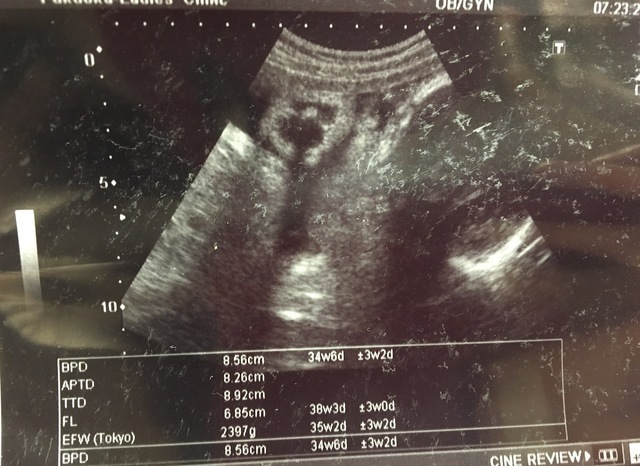

34週4日(34w4d・男の子)|fmk23 さん(29歳)

エコー写真撮影時のエピソード:

性別の判断がなかなかつかず、20週を過ぎてやっと男の子っぽいと言われましたが、いつもエコーで見るとちんちんを隠していて、ハッキリ確認することができませんでした。

34W4dのこの時にはタマタマがハッキリ見えて、確実に男の子だとお墨付きをいただいた記念すべきエコー写真です!